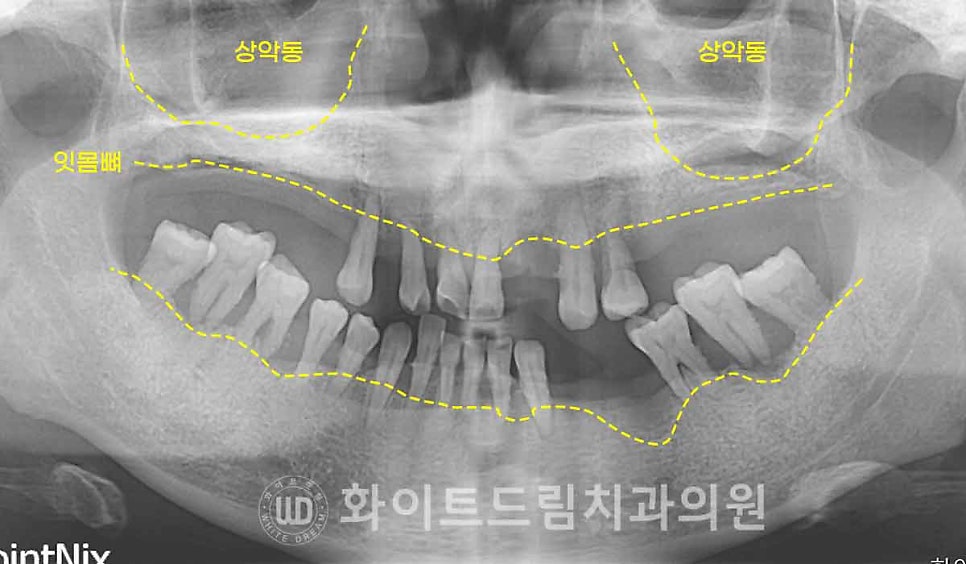

준비한 케이스의 초진 X-RAY 사진입니다.

이미 많은 치아들이 상실되었고

심한 치주염으로 잇몸뼈의 높낮이가 들쭉날쭉한 상태입니다.

치조골이 파괴된 범위와 치조골로 잇몸뼈가 파괴된 시기가 다르기 때문에

만성 치주염이 있으신 분들은 이렇게 잇몸뼈의 높낮이가 맞지 않는 특징이 있습니다.